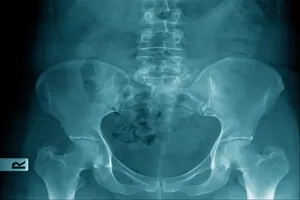

좌골신경통은 좌골신경이 압박되거나 자극받아 발생하는 통증을 말합니다. 좌골신경은 인체에서 가장 길고 큰 신경으로, 허리 아래쪽에서 엉덩이를 지나 다리 뒤쪽까지 이어집니다.

주로 허리 디스크, 척추관 협착증, 엉덩이 근육 문제 등이 원인이 됩니다. 증상이 심해지면 일상생활에 큰 불편을 초래할 수 있으니 조기 대처가 중요합니다.